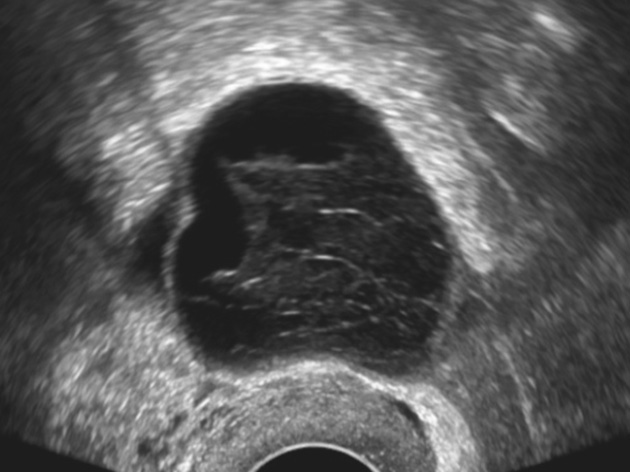

К «практически наверняка доброкачественным» относятся образования, имеющие «классическую» эхографическую картину доброкачественного образования (простая и однокамерная киста, геморрагическая киста, эндометриома, дермоидная киста и фиброма) (рис. 1–6). Понятие однокамерной кисты относительно новое и подразумевает наличие в полости кисты ≥1 неполной перегородки, локальных утолщений на стенке высотой до 3 мм, внутренних эхо в полости (рис. 2). Одиночная тонкая (≤3 мм) перегородка в полости кисты считается доброкачественной находкой [22].

Рис. 1. Простая киста яичника. Анэхогенное аваскулярное образование с ровными тонкими стенками, без солидного компонента и перегородок

Fig. 1. Simple ovarian cyst: an anechoic avascular lesion with smooth thin walls, without a solid component and septations

Рис. 2. Однокамерная киста яичника. Киста с одиночной неполной перегородкой и внутренним эхо

Fig. 2. Uniloculated ovarian cyst: a cyst with one incomplete septum and internal echoes